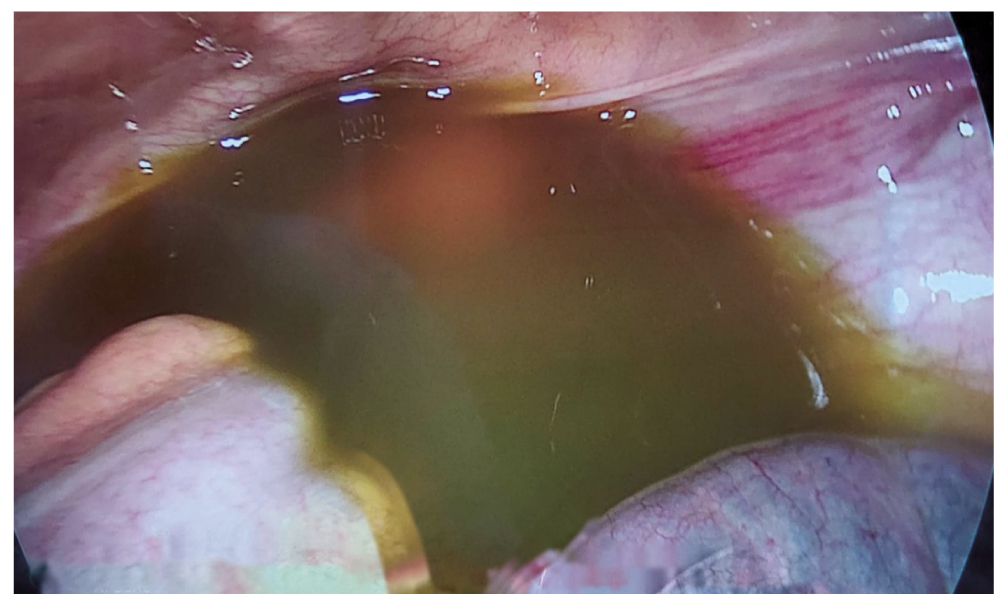

При ревизии брюшной полости в подпечёночной области обнаружен выраженный воспалительный перипроцесс — инфильтрат, фиксированный к передней брюшной стенке, пилорическому отделу желудка по большой и малой кривизне, луковице двенадцатиперстной кишки, печёночно-желудочной связке и сальнику. Выявлены множественные фибринозные наложения и гнойно-некротические ткани. В области шейки и мешка Хартмана желчного пузыря серозная оболочка общего печёночного протока стекловидно отёчная и покрыта фибрином. Для исключения прикрытой перфорации желудка или двенадцатиперстной кишки, интраоперационно проведена эзофагогастродуоденоскопия — патологии не выявлено. После разделения инфильтрата и рассечения спаек выделена круглая связка печени. Связка утолщена до размеров 3×4 см, багрово-чёрного цвета с гнойно-некротическими тканями (рис. 2). Проведено тотальное иссечение некротизированной круглой связки на всем протяжении (рис. 3). Изменённая часть брюшины с предбрюшинной жировой клетчаткой также резецированы. Брюшная полость санирована 0,9% раствором хлорида натрия.

Рис. 2. Круглая связка печени и массивные фибринозные наложения.

Fig. 2. Round ligament of the liver and massive fibrin deposits.